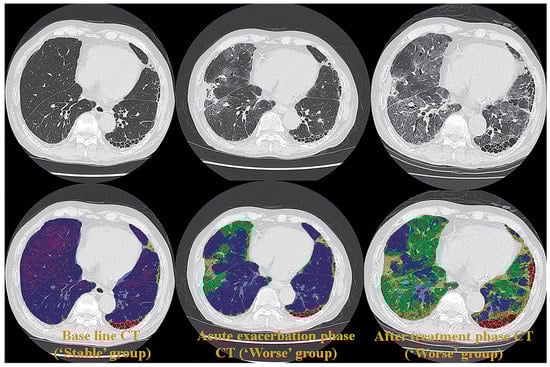

Although the potential of Xe or krypton (Kr) to function as gas contrast media has been known since the 1960s [93,94,95], they were not academically or clinically used for pulmonary functional imaging until 2008. Oxygen-enhanced MRI and hyperpolarized noble gas MRI were reported to be useful for ventilation-based pulmonary functional imaging in the late 1990s [65,66,67,68,69,70]. For this reason, Xe- or Kr-enhanced ventilation CTs have mainly been used for pulmonary functional imaging for in vitro or in vivo studies after the clinical installation of DECT since 2008 [67,68,73,87,96,97,98,99,100,101,102,103,104,105,106,107,108,109,110,111]. Since that time, DECT has been mainly used by dual-source CT systems for patients with COPD or asthma [67,68,73,87,96,97,98,99,100,101,102,103,104,105,106]. However, no studies on the use of ADCT for Xe-enhanced DECT were published until 2023. In contrast to DECT, subtraction ADCT was demonstrated to be as effective as subtraction CT for the visualization of xenon enhancement for in vitro or in vivo studies and for pulmonary functional loss evaluation in comparison with the use of DECT or Kr-81m ventilation SPECT/CT for in vivo studies [107,108,109,110,111]. Moreover, these in vivo studies have demonstrated the potential of Xe-enhanced subtraction ADCT for regional ventilation evaluation or therapeutic effect assessment for smokers, COPD patients, asthmatics, or lung cancer patients [107,108,109,110,111] (Figure 4).

Figure 4.

A 75-year-old male smoker with “Moderate COPD” (58 pack-years, FEV1/FVC%: 55%, %FEV1: 58%) (permission from reference [108]). (A) (L to R: cranial to caudal): Thin-section CT shows a heterogeneously distributed low attenuation area due to pulmonary emphysema. (B) (L to R: cranial to caudal): DECT shows heterogeneous xenon enhancement within the lung and areas of reduced xenon enhancements corresponding well to the distribution of the areas of low attenuation. Total ventilation defect score was 66, and functional lung volume was 65.8%. (C) (L to R: cranial to caudal): Subtraction CT shows heterogeneous xenon enhancement within the lung and areas of reduced xenon enhancement corresponding well to the distribution of the areas of low attenuation. Total ventilation defect score was 88, and functional lung volume was 53.7%. (D) (L to R: cranial to caudal): Co-registered Kr–81m ventilation SPECT/CT shows markedly heterogeneous uptakes within the lung. Regional uptakes correspond well to areas of low attenuation. Total ventilation defect score was 84, and functional lung volume was 55.8%. Regional uptakes of Kr–81m show better correspondence to xenon enhancement on subtraction CT than on DECT.

In addition, inspiratory and expiratory (inspiratory/expiratory) Xe-enhanced subtraction CT with hybrid-type IR has been found to be effective for the assessment of the regional ventilation changes in lung cancer patients due to smoking-related COPD or surgical treatment [110,111]. Although Xe-enhanced subtraction ADCT as well as DECT with dual-source CT are considered to be useful for pulmonary ventilation imaging, cold Xe or Kr has currently not been approved as contrast media for ventilation CT because they were only approved as contrast media for brain CT by the United States Food and Drug Administration, the Japan Pharmaceuticals and Medical Devices Agency, or regulatory authorities in other countries. It is, therefore, vital to obtain, in the near future, the regulatory approval of Xe and Kr as gas contrast media for pulmonary functional imaging, whether Xe-enhanced subtraction ADCT or DECT with dual-source CT are applied.